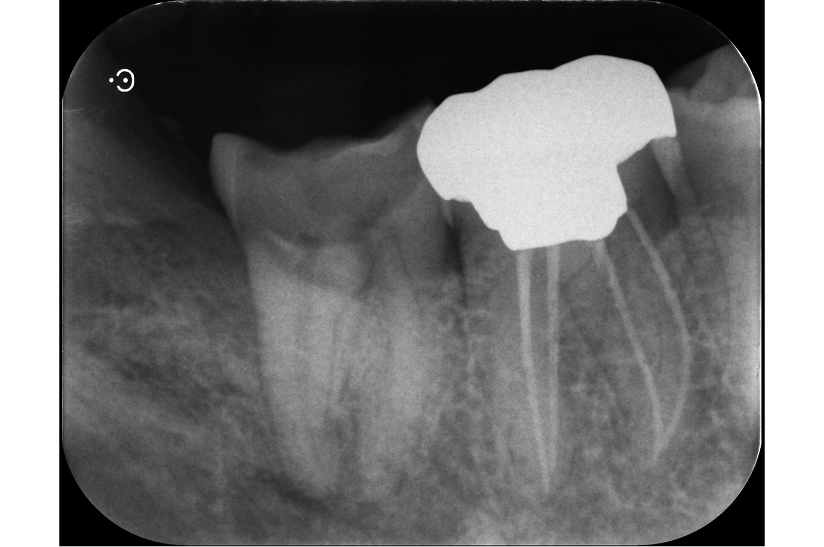

再根管治療で奥歯を残した症例

タップで写真の拡大ができます。

Before

After

主訴

噛むと違和感がある。

治療内容

リトリートメント(再根管治療・大臼歯)

ファイバーポストコア

治療期間

1ヶ月

治療費用

198,000

治療の

リスク

根尖部透過像が完全に消失しない可能性があります。